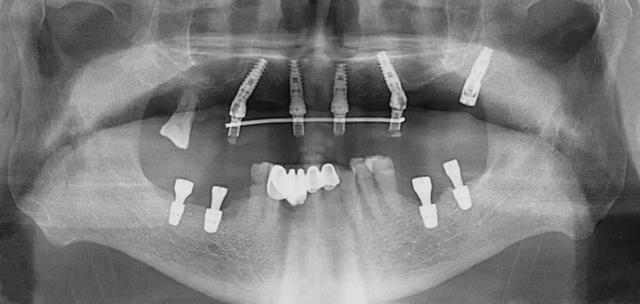

口腔科李德仁主任為老人仔細(xì)檢查了口腔情況,由于缺牙時(shí)間太久,牙床骨量極少,正常的種植修復(fù)需要植骨,手術(shù)創(chuàng)傷大而且半年后才能鑲牙吃飯。建議他進(jìn)行數(shù)字化導(dǎo)板種植,可以不用植骨而且當(dāng)天就能戴牙吃飯,手術(shù)簡(jiǎn)單,創(chuàng)傷小。老人和孩子很信任的接受了李主任的種植方案:上牙床種植5顆,下牙床種植4顆,當(dāng)天戴牙吃飯。

下午2點(diǎn)開(kāi)始手術(shù),歷經(jīng)90分鐘,一共植入9顆種植體,全程。下午7點(diǎn)用了10多分鐘就完成了假牙安裝,假牙與牙床渾然一體,像是重新長(zhǎng)出的牙齒一般。

全口缺牙一日重建種植手術(shù)有以下優(yōu)點(diǎn):使用CT導(dǎo)板定位,在骨量好的位置種植,一般不需植骨,手術(shù)創(chuàng)傷小,手術(shù)時(shí)間短,愈合快,基本上沒(méi)有疼痛。拔牙同時(shí)種植牙,當(dāng)日戴臨時(shí)全口固定式假牙吃飯。